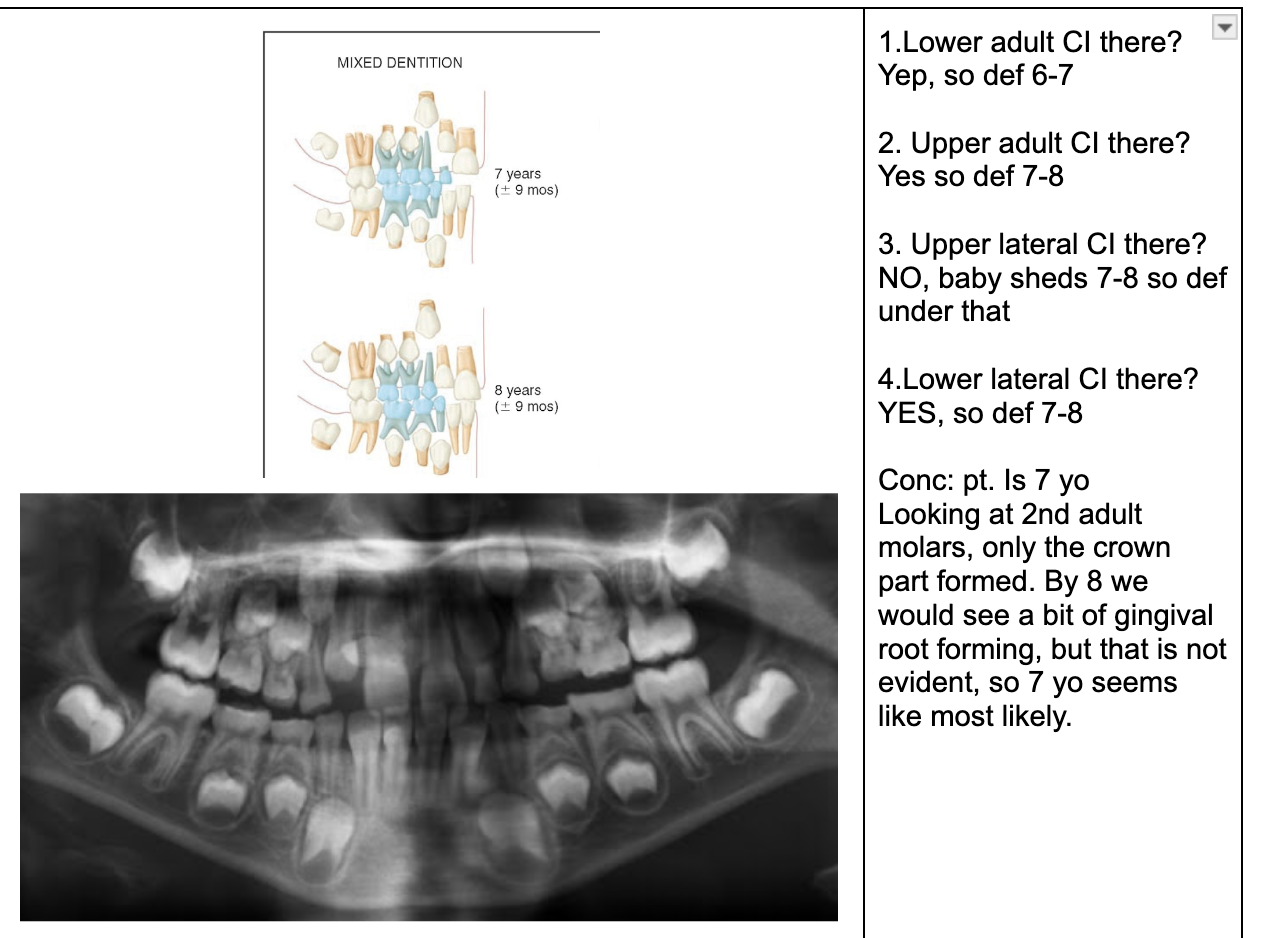

1.lower adult CI there? YES, so def 6-7

1. Upper Ad. Ci there? NO, so either 6-7 or under

Last molar crown not really formed so 6?

NOTE- THE 8’s - crown starts developing at 9 yo.